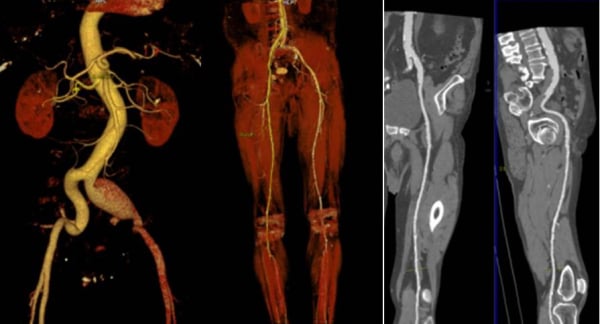

Αξονική Αγγειογραφία (CTA)

Η Αξονική Αγγειογραφία (CTA) είναι μια ιατρική εξέταση που χρησιμοποιεί τεχνολογία της υπολογιστικής τομογραφίας (CT) για να παράγει λεπτομερείς εικόνες των αγγείων. Η CTA είναι ένα αποτελεσματικό μέσο για την αξιολόγηση του αγγειακού συστήματος και χρησιμοποιείται συχνά για την εξέταση των αγγείων σε διάφορα μέρη του σώματος.

Η διαδικασία της CTA περιλαμβάνει τη χρήση ένος CT scanner και ενός υλικού αντίθεσης που εισέρχεται στον οργανισμό για να κάνει τα αγγεία πιο ορατά στις εικόνες. Ο ασθενής θα τοποθετηθεί στο κρεβάτι του scanner, και η συσκευή θα κινηθεί γύρω του για τη λήψη σειράς εικόνων.

Η CTA μπορεί να χρησιμοποιηθεί για την αξιολόγηση των αγγείων σε διάφορες περιοχές του σώματος, συμπεριλαμβανομένων:

- Καρδιακών Αγγείων (Coronary Arteries): Χρησιμοποιείται για τον εντοπισμό πιθανών στενών ή πλακών στις αρτηρίες που εφοδιάζουν την καρδιά.

- Κεφαλής και Τραχήλου (Head and Neck): Χρησιμοποιείται για την αξιολόγηση των αγγείων στο κεφάλι και τον λαιμό.

- Κοιλιακού Χώρου (Abdomen): Χρησιμοποιείται για τον έλεγχο των αγγείων στην περιοχή της κοιλιάς, συμπεριλαμβανομένων της κοιλιακής αορτής και των αγγείων των οργάνων της κοιλιάς.

- Άνω και Κάτω Άκρων: Χρησιμοποιείται για την αξιολόγηση των αγγείων στα άνω και κάτω άκρα.

Η CTA παρέχει λεπτομερείς εικόνες που μπορούν να βοηθήσουν τους ιατρούς να αξιολογήσουν την κατάσταση των αγγείων και να διαπιστώσουν πιθανά προβλήματα, όπως στένωση ή ανεύρυση των αγγείων.